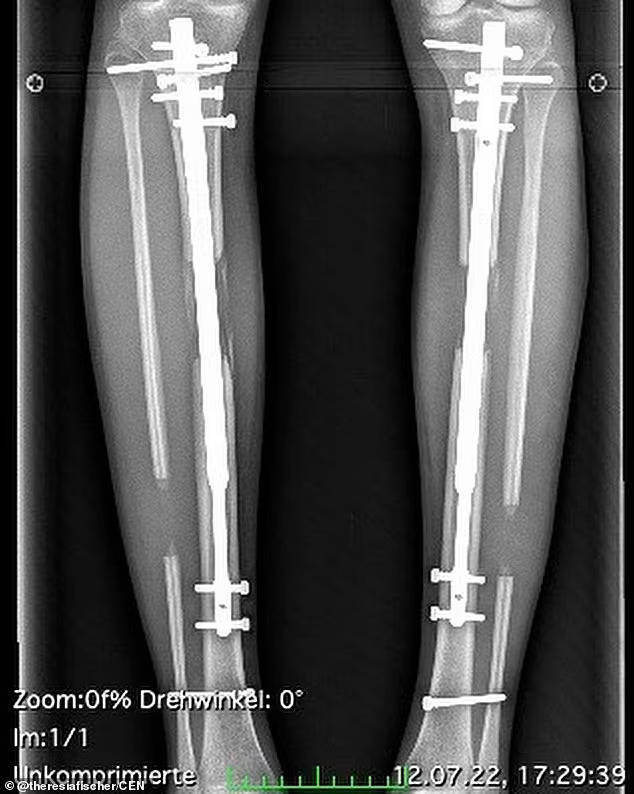

Лекарите вметнале прилагодливи телескопски шипки во нејзините потколеници и постепено ги вртеле додека нејзините нозе не биле подолги. Манекенката потоа имала уште една операција минатиот март за да ги издолжи нозете по втор пат за дополнителни 3 сантиметри. Трошоците за двете процедури заедно достигнале повеќе од 162.000 долари.

Таа го објасни процесот на операција за германскиот весник „ Билд“ и рече: „За време на процедурата, коската на потколеницата е чисто скршена, мускулите на потколеницата се поделени и во секој случај се користи телескопска прачка. Се срамам затоа што се согласив на операција која не требаше да ја направам“.